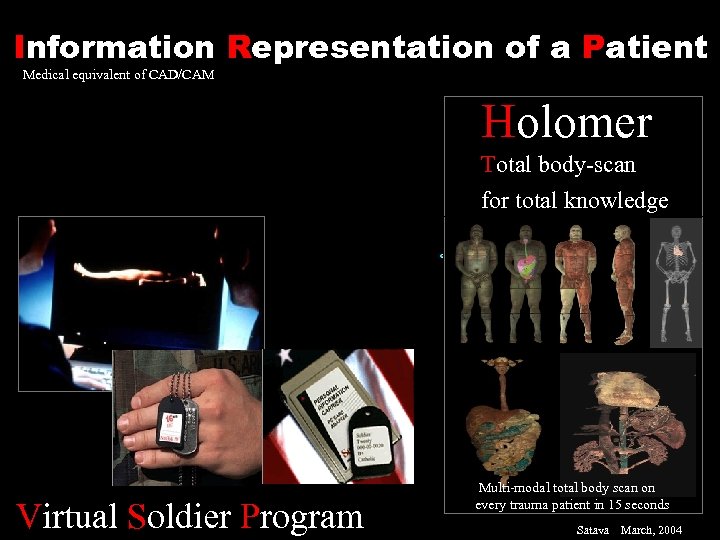

Information Representation of a Patient Medical equivalent of CAD/CAM Holomer Total body-scan for total knowledge Virtual Soldier Program Multi-modal total body scan on every trauma patient in 15 seconds Satava March, 2004

Information Representation of a Patient Medical equivalent of CAD/CAM Holomer Total body-scan for total knowledge Virtual Soldier Program Multi-modal total body scan on every trauma patient in 15 seconds Satava March, 2004